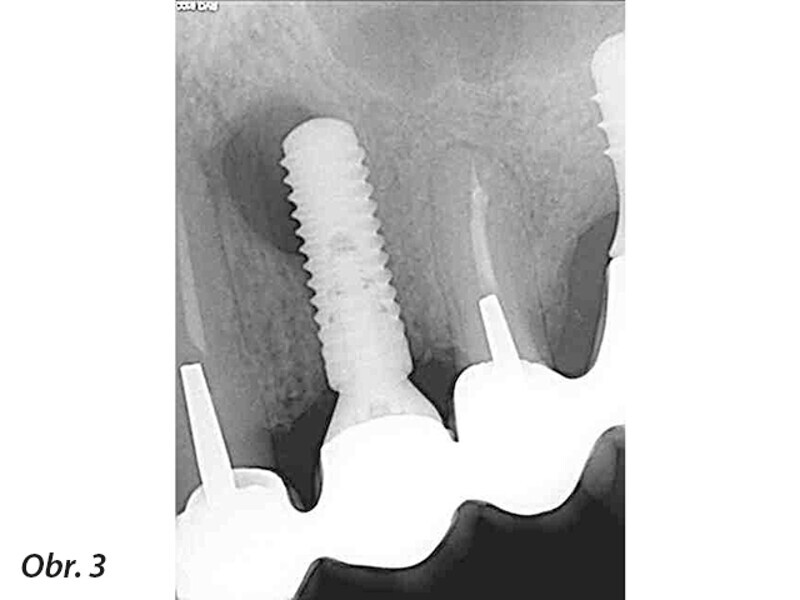

Periapikální léze implantátů a retrográdní periimplantitis – dva stavy nepříliš zdokumentované